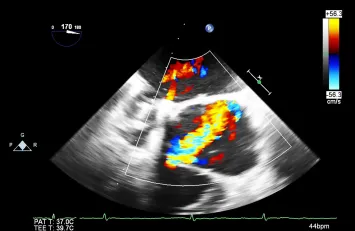

Advanced Echocardiography: Using TTE, TEE, and 3D Echo imaging to visualize cardiac anatomy and function in detail for accurate diagnosis.